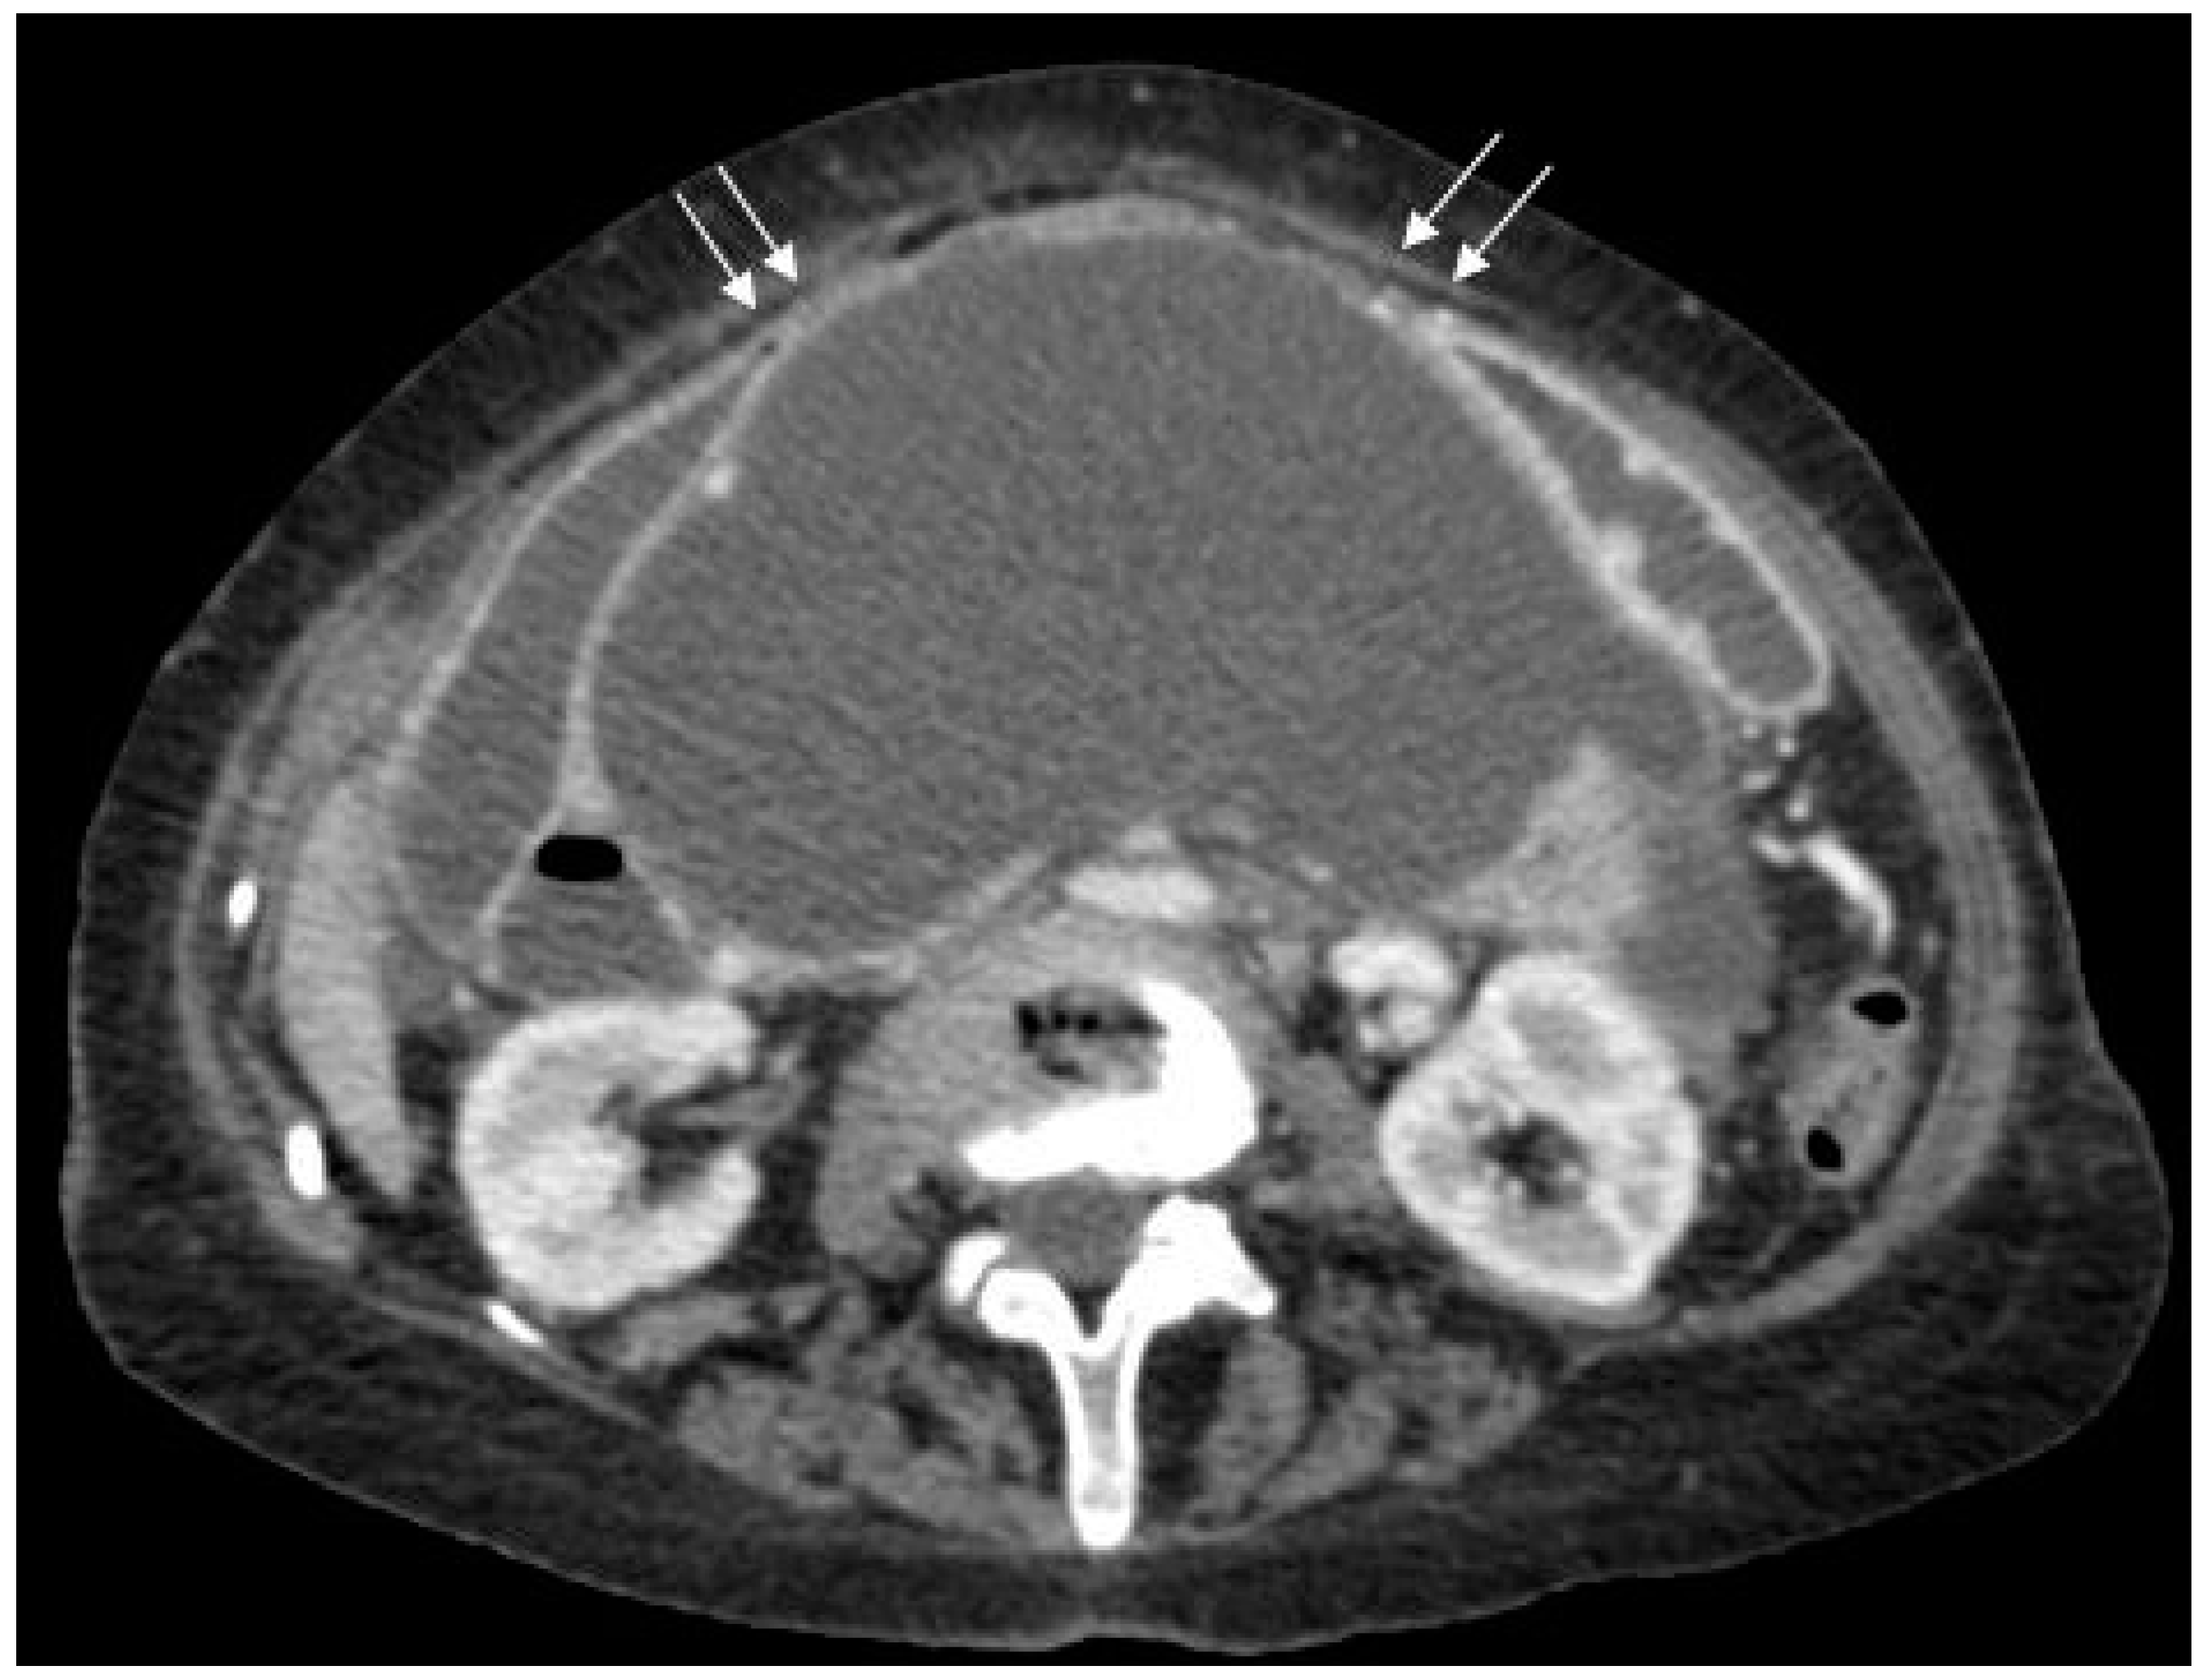

Figure 1.

Axial post-contrast computed tomography (CT) scan of the upper abdomen showing a large pancreatic pseudocyst with the stomach (arrows) stretched anteriorly over it.